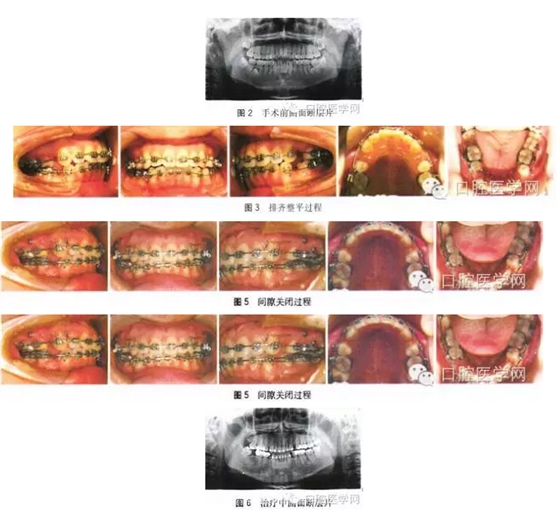

3、X線檢查

手術(shù)前曲面斷層片:所有恒牙均存在,36、46牙根遠(yuǎn)中各存在一顆多生牙且36、46遠(yuǎn)中根已出現(xiàn)病變吸收,18、28、38、48存在,48近中阻生。手術(shù)后曲面斷層片:所有恒牙均存在,已于外院拔除多生牙,46遠(yuǎn)中根吸收明顯,47近遠(yuǎn)中根基本完全吸收,36遠(yuǎn)中根吸收達(dá)1/2,四顆智齒存在且形態(tài)良好,48近中阻生,頭影測量結(jié)果見表1。

6、矯治過程

全口粘接0.022英寸(1英寸=2.54 cm)MBT直絲弓固定矯治器,下頜36、45、46帶環(huán),焊接固定舌弓增強(qiáng)支抗,17、27、37粘接頰面管,48牙合面粘接舌側(cè)扣,固定舌弓遠(yuǎn)中拉鉤牽引豎直48,初始弓絲為0.012英寸。待48頰面暴露后粘接頰面管,依次應(yīng)用0.016、0.018、 0.018×0.025英寸鎳鈦方絲初步排齊整平上下牙列并繼續(xù)豎直48。

第 8個月上頜植入支抗種植釘,更換0.019×0.025英寸不銹鋼方絲,下頜更換0.018×0.025英寸不銹鋼方絲,去除部分固定舌弓但保留45與 46的聯(lián)接,滑動法內(nèi)收前牙并近中移動48。治療過程中48出現(xiàn)舌傾,配合16、17、48交互牽引。第27個月拔牙間隙關(guān)閉,48移動到位,精細(xì)調(diào)整。第32個月矯治結(jié)束,上下頜壓膜保持器保持,定期復(fù)查。